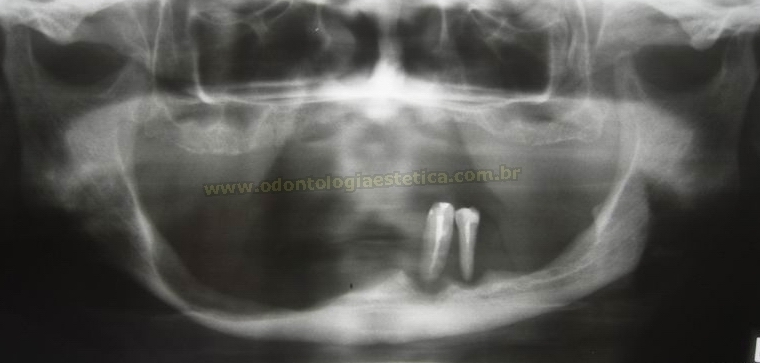

Tratamento  reabilitador combinado de maxila e mandíbula com implantes osseointegráveis sobre bases ósseas antes severamente atróficas e reconstruídas por enxertia óssea autógena de calota craniana, em paciente do sexo feminino, com idade relativamente avançada para um procedimento desse porte, vindo atestar que, cada vez mais a ciência e a prática clínica caminham juntas no intento de proporcionar melhoria na qualidade de vida dos pacientes acometidos por essas patologias.

Limitações do caso: Seria totalmente inviável realizar o tratamento  se a reconstrução das bases tivesse sido rejeitada como a opção ideal para a solução dos problemas pré-existentes, devido às extensas perdas ósseas generalizadas sofridas ao longo dos anos e também da fragilidade da estrutura mandibular, principalmente do lado direito.

implantes sobre  enxerto de calota occipital rx panoramico raio x panoramica radiografia panorâmica após enxerto reforço metálico por placas e implantes após tratamento reabilitadpor implantes em maxila e mandíbla severame atróficas